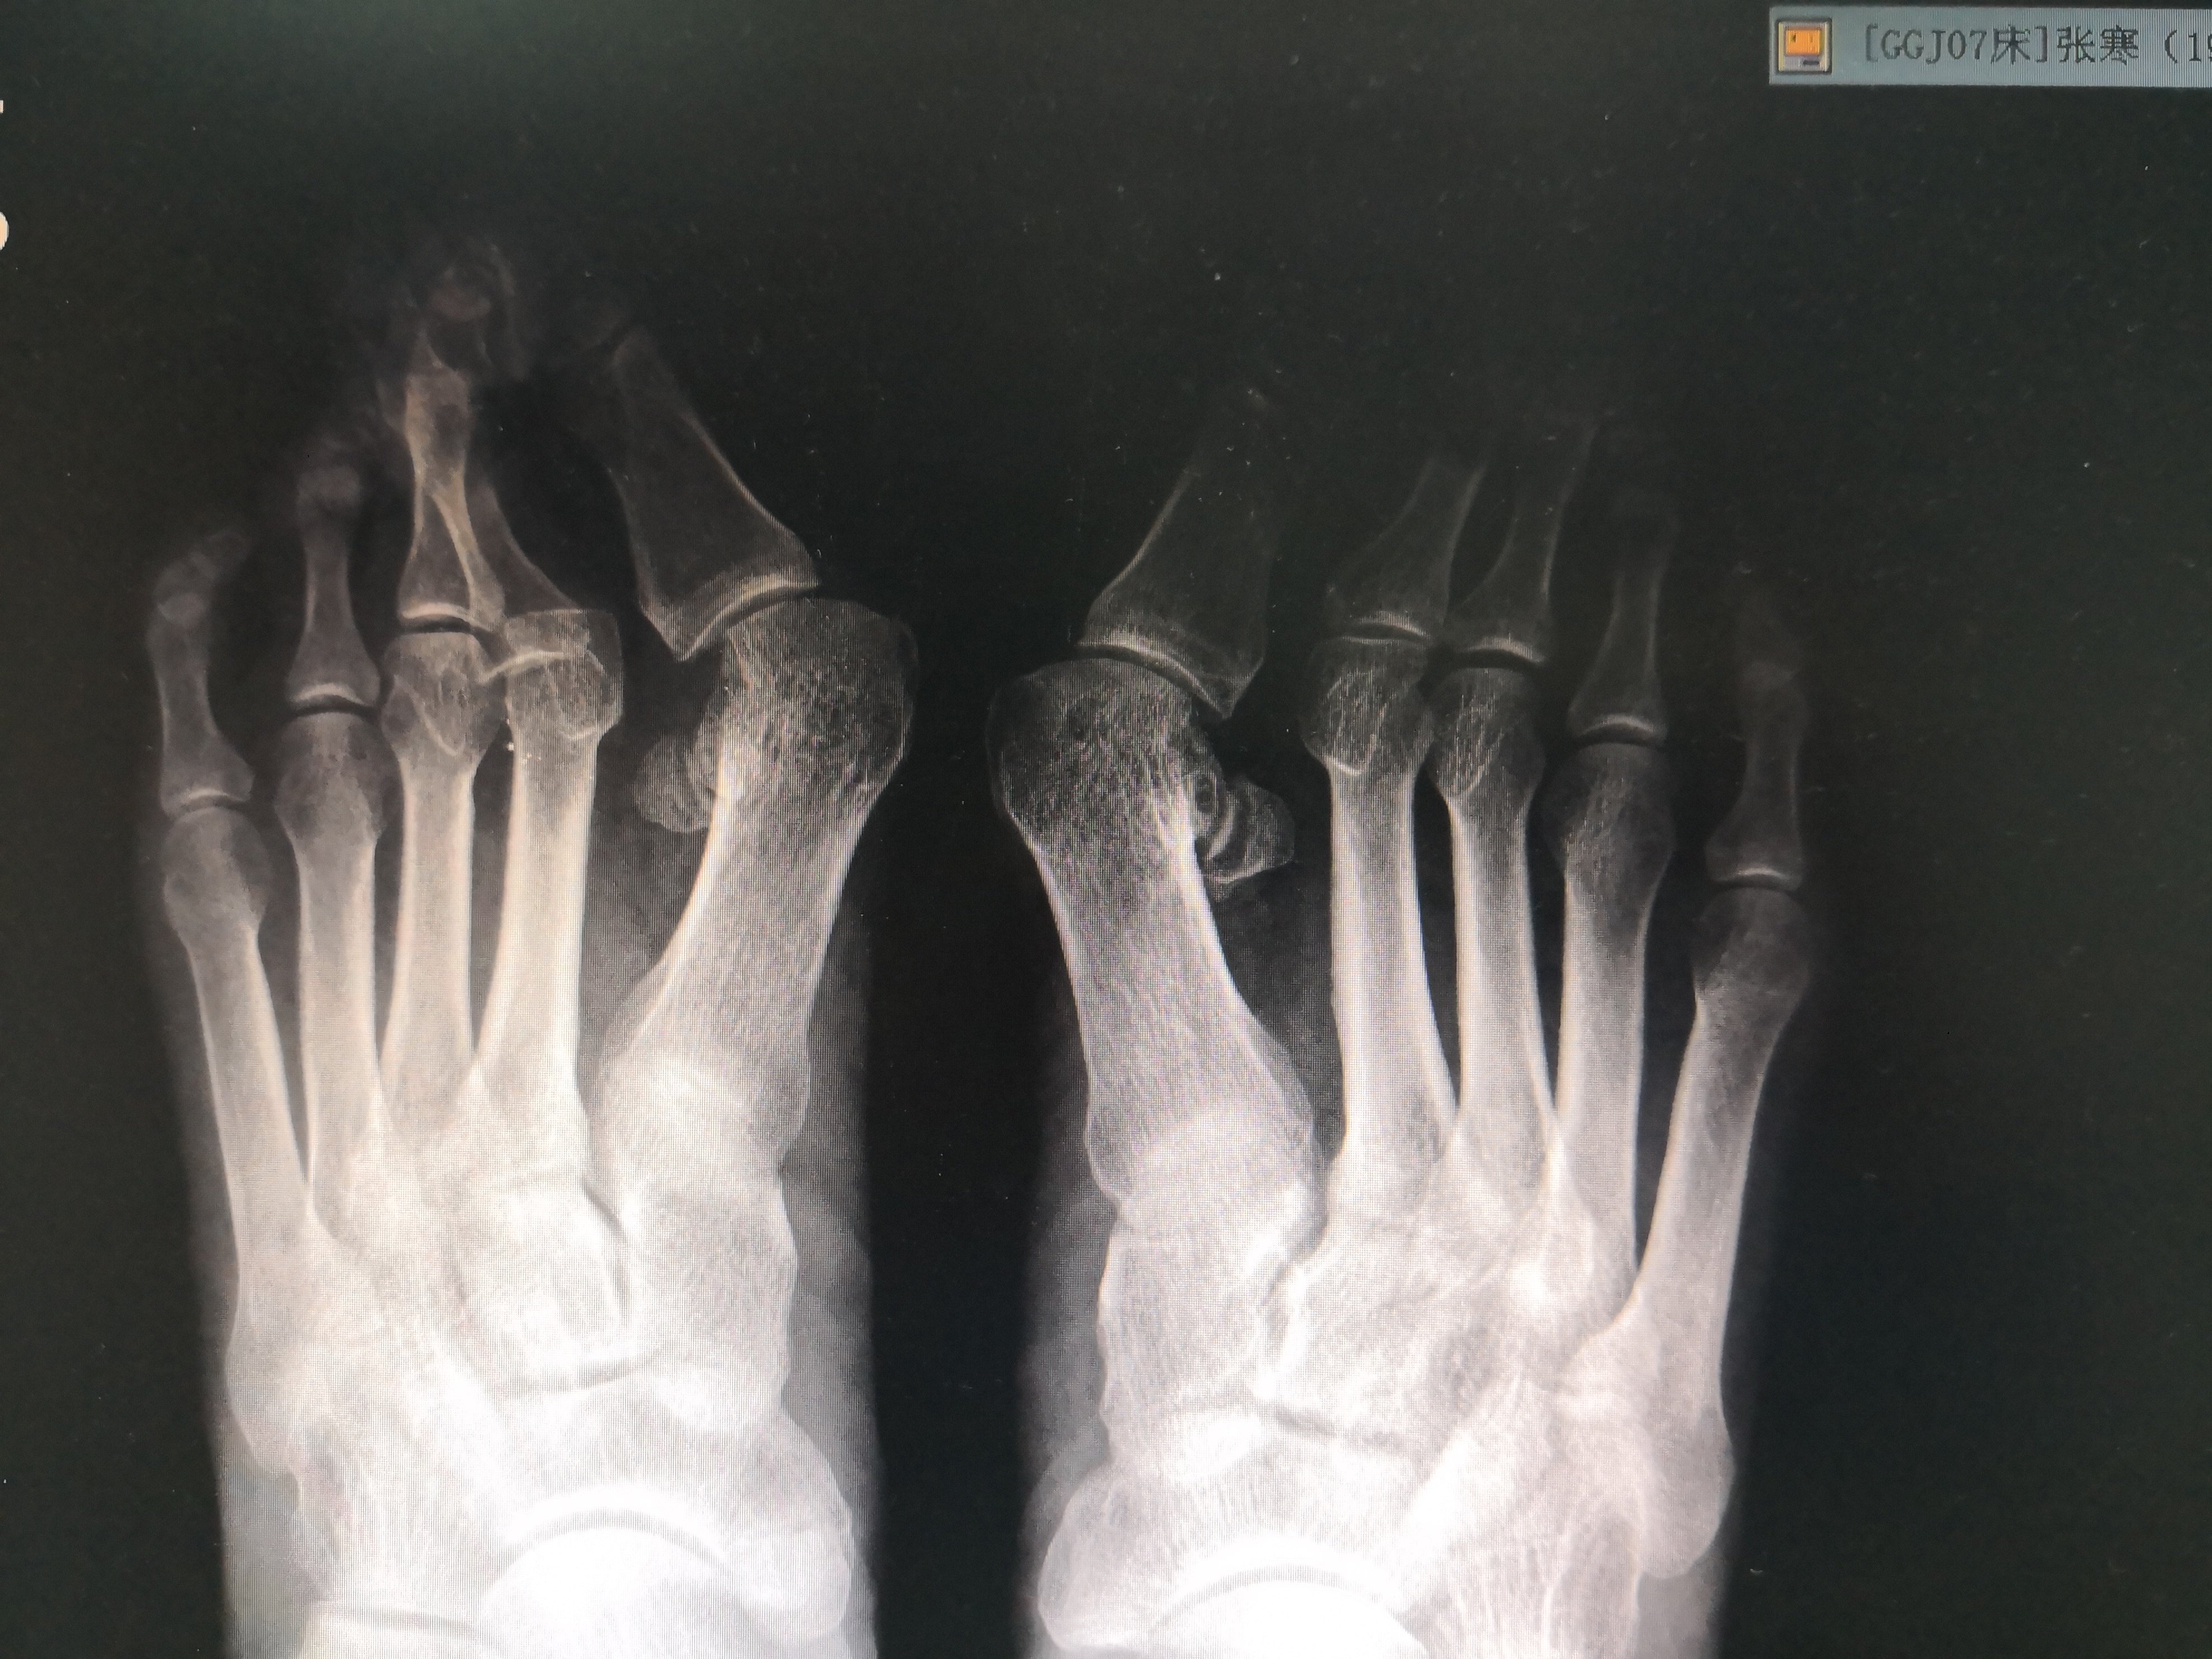

一例双足拇外翻 [病例帖]

图片尺寸4608x3456